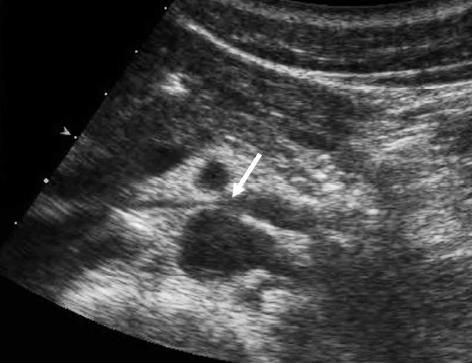

호두까기증후군 호두까기증후군

[논문 발췌]

호두까기증후군은 왼쪽 콩팥 정맥이 대동맥과 상장간동맥 사이에서 눌려 콩팥 안에 압력이 증가하면서 미세한 콩팥 조직과 혈관에 손상이 생기는 질환을 일컫는다.

호두까기증후군이라는 질환명은 두 동맥이 콩팥 정맥을 누르는 모양새가 마치 호두까기 기계의 집게처럼 보이고, 콩팥 정맥이 호두처럼 보인다고 해서 붙여졌다.